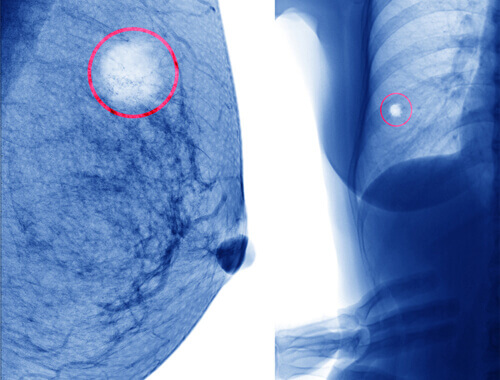

Torbiel sutka to nagromadzenie płynu we wnętrzu piersi. Ma formę małej torebki, zwykle wielkości ciecierzycy lub mniejszej, która zwykle zawiera płyn.

Podczas gdy większość torbieli sutka jest wypełniona płynem, istnieją również torbiele łagodne, które są bardziej zbite w swojej strukturze.

Istnieje inny rodzaj torbieli zwany gruczolakowłókniakiem. Zwykle tego typu torbiele są bezobjawowe i bezbolesne. Można je odkryć podczas badania piersi, wyczuwając mały, twardy, ruchomy guzek w piersi.

Kiedy go dotkniesz, na ogół będzie on gładki lub nieco szorstki, gdy jest spowodowany gruczolakowłókniakiem z płatami. Są to łagodne odmiany guza. Włókniakogruczolaki występują, gdy dochodzi do nadmiernego wzrostu tkanki sutkowej. Ponadto, chociaż można je pomylić z opisanymi powyżej torbielami sutka, są one odmienne w swojej formie.